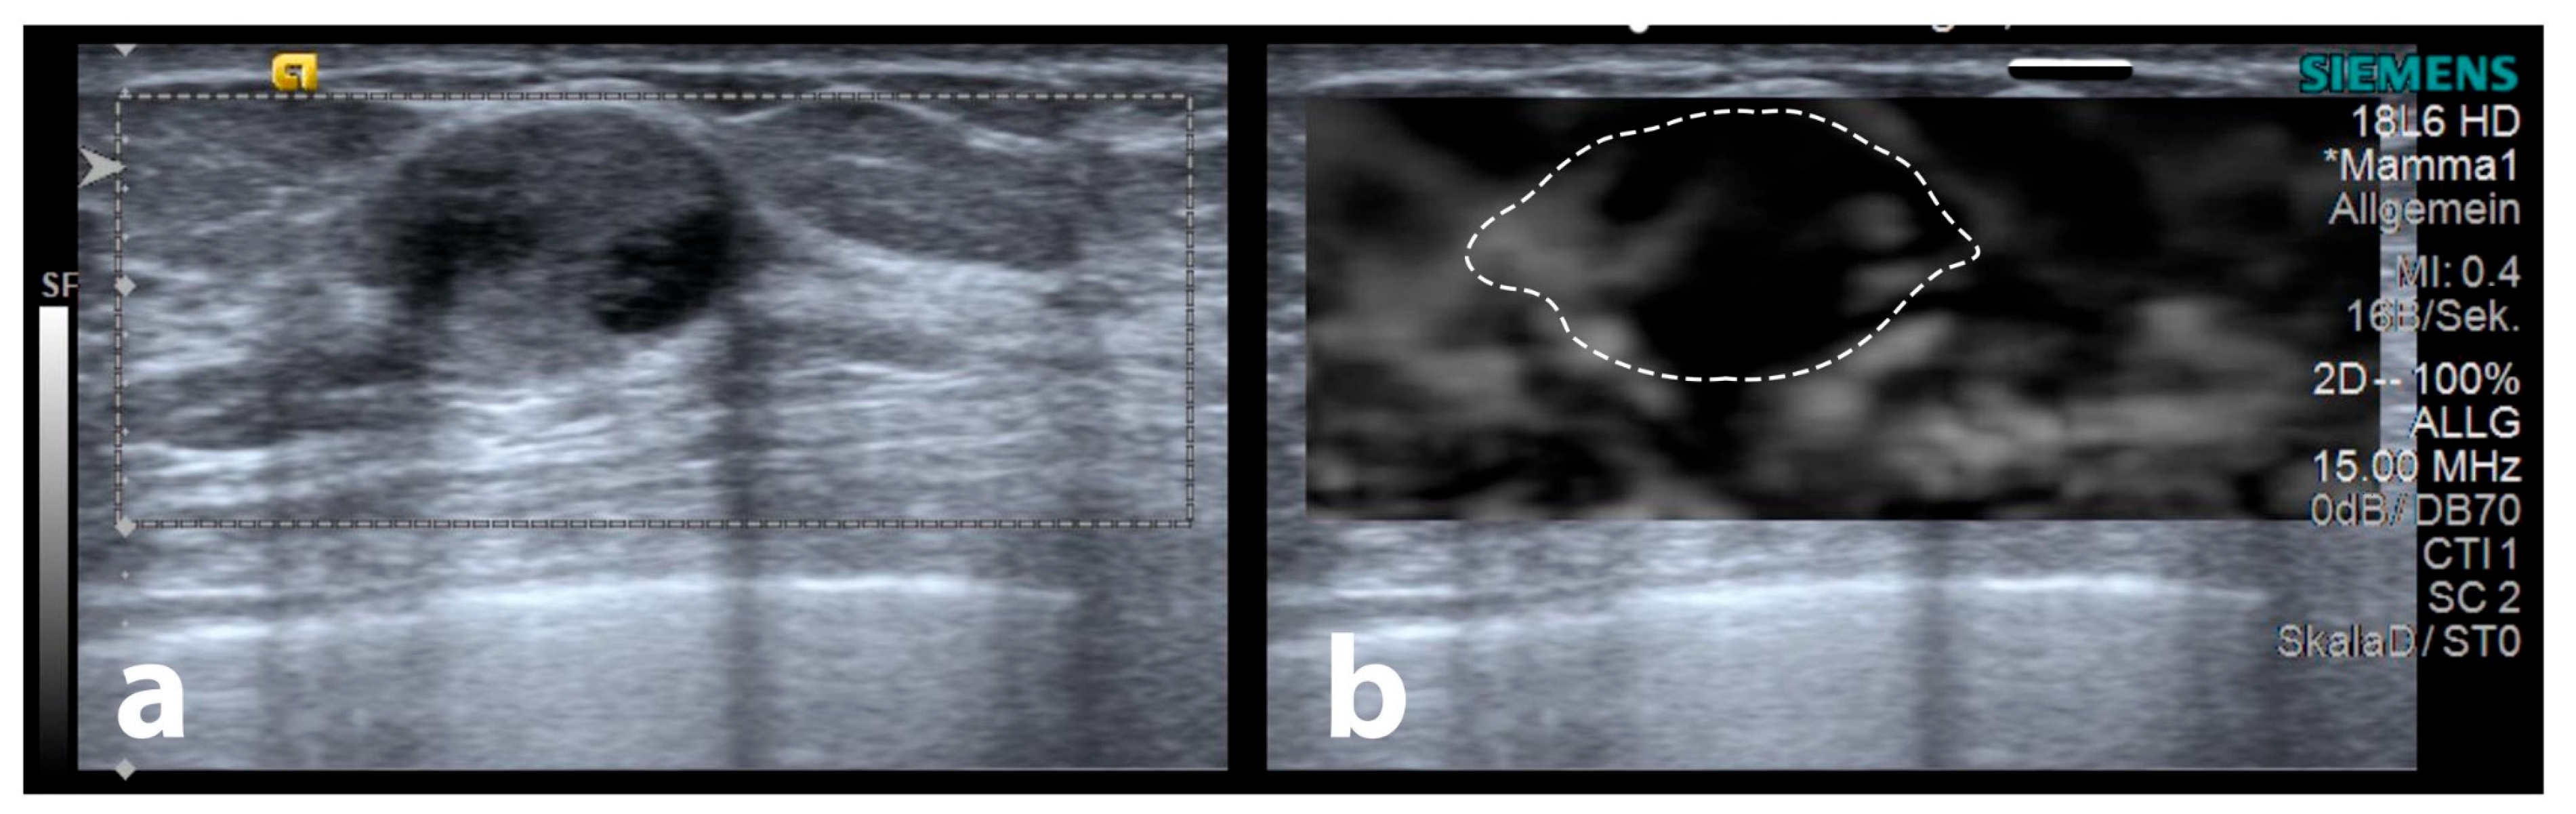

2.3. Ultrasound Examination Procedure

2.6. Maximum Elastographic Peritumoural Halo Depth (SEPHmax) Measurement